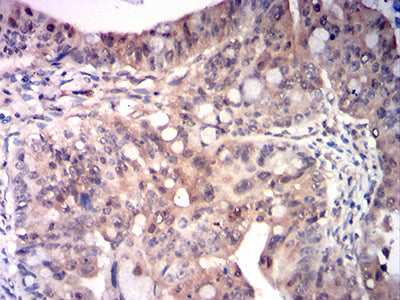

Immunohistochemical analysis of paraffin-embedded human bladder cancer tissues using RRM1 mouse mAb with DAB staining.

Immunohistochemical analysis of paraffin-embedded human rectum cancer tissues using RRM1 mouse mAb with DAB staining.